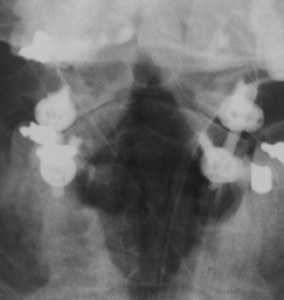

Rheumatoide-Arthritis-Stabilisierung-kor

Operative Stabilisierung des 1. und 2. Halswirbels mit Schrauben und Stäben bei zugrunde liegender Rheumaerkrankung.